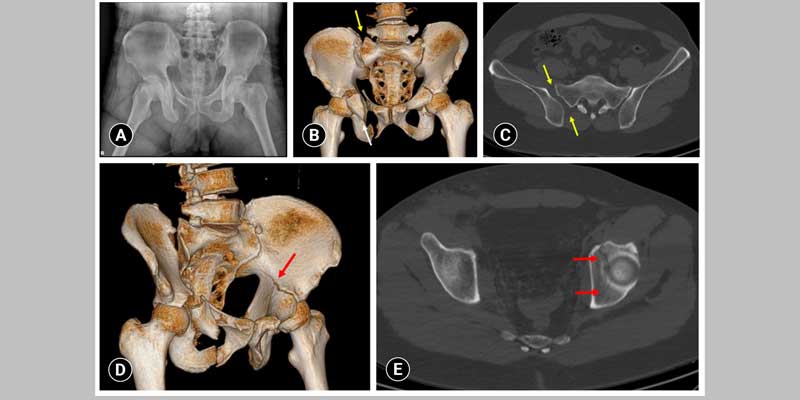

pelvi acetabulum fracture

Dr. Ramakant Bhivsan offers specialized care for Pelvi-Acetabulum Fractures, which are complex injuries involving the pelvic bone and hip socket, often resulting from high-impact trauma. With advanced training in orthopedic trauma management, Dr. Bhivsan provides precise surgical intervention to realign and stabilize the fractured bones, ensuring optimal joint function and long-term recovery. His comprehensive approach includes detailed imaging, careful pre-operative planning, and post-operative rehabilitation tailored to each patient’s condition. Dr. Bhivsan is committed to delivering high-quality care that minimizes complications, restores mobility, and helps patients regain their independence after serious pelvic injuries.